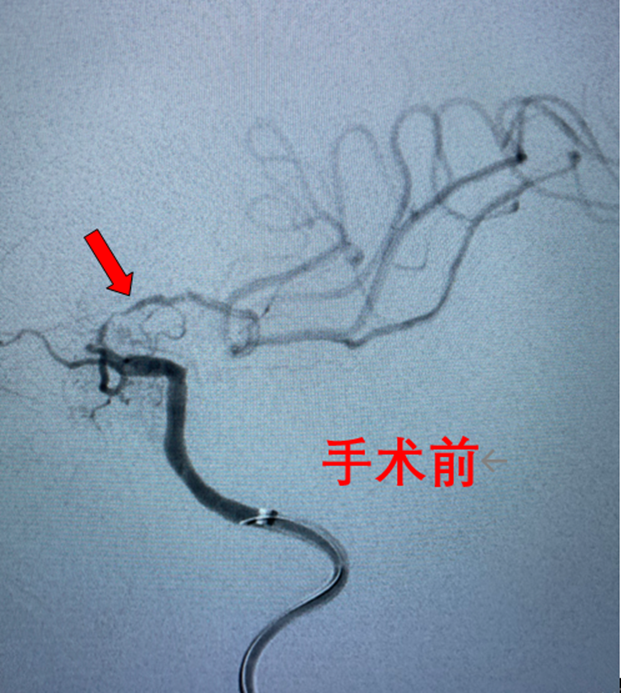

随着时间的推移,陈大爷病情不断加重,突然有一天他失去了意识,家人赶紧将他送到了自贡四院神经内科救治。经过专家的检查和诊断,陈大爷的病因找到了——左侧颈内动脉末段堵塞,导致了我们大家熟知的脑梗。

做好术前准备后,陈大爷进入介入手术室,神经内科医务人员成功为其完成了“左侧颈内动脉末段血管成形、支架植入术”。

术后,陈大爷头晕、行走不稳等症状消失,恢复到正常状态。